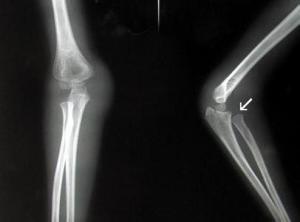

孟氏骨折(Monteggia fracture)系指尺骨近侧1/3骨折合并桡骨头脱位而言。为Monteggia于1814年首先加以描述,后即以其名称呼此种骨折脱位。